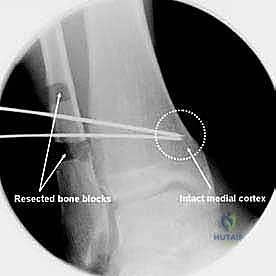

- قص العظم (Osteotomy): باستخدام منشار جراحي دقيق وموجهات خاصة، يتم قص عظم الظنبوب (وفي بعض الأحيان عظم الشظية أيضاً) بالزاوية التي تم تحديدها مسبقاً في التخطيط الثلاثي الأبعاد.

- تصحيح المحور: يتم فتح أو إغلاق الشق العظمي للوصول إلى المحور الميكانيكي السليم للكاحل. يتم التحقق من ذلك داخل غرفة العمليات باستخدام جهاز الأشعة السينية الفلوروسكوبي (C-arm).